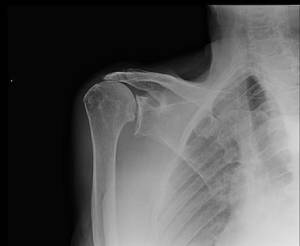

Rotator cuff arthropathy is characterized by the combination of

- rotator cuff insufficiency

- glenohumeral cartilage destruction

- superior migration of the humeral head

- subchondral osteoporosis

- humeral head collapse